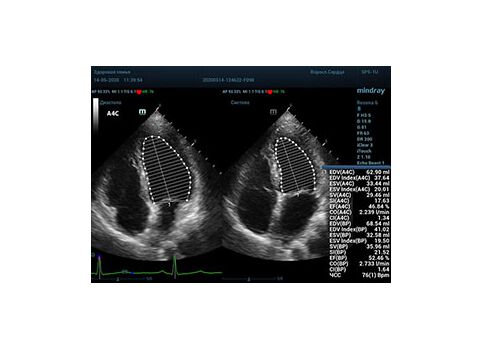

С появлением В режима реализовалась возможность визуализации всех сегментов миокарда из парастернальных и апикальных сечений. Метод Teicholtz в широкой практике сменился методом дисков. Метод дисков, или метод Simpson, позволяет разбить левый желудочек на 20 дисков, с расчетом объема каждого из них. Используя 2 перпендикулярных сечения, апикальные двух и четырех камерное, мы приближаемся к значению реального объема левого желудочка. Исследователь обводит интерфейс эндокард – кровь в фазу диастолы и фазу систолы. Линия простирается от кольца митрального клапана и до кольца митрального клапана, четко разграничивая объем желудочка от предсердия. Для достоверного изменения необходимо использовать ЭКГ канал.

Что могут предложить современные приборы? Приборы нашего времени являются мощными вычислительными машинами, способными обрабатывать полученную информацию даже без помощи человека. Система автоматического вычисления фракции выброса – AUTO EF на приборах серии Resona компании Mindray сделает все за вас. За пару секунд прибор сам отыщет нужную фазу сердечного цикла и произведёт измерение и расчеты, а также покажет график изменения объема в сердечном цикле. От Вас требуется только получить качественное 4С и 2С сечение. Впрочем, прибор всегда оставляет возможность коррекции, если доктор имеет свое мнение на расположение точек планиметрии или момента измерения по ЭКГ каналу.